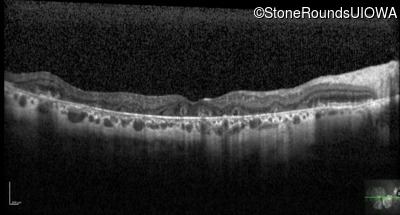

Optical Coherence Tomography - Right - 20/25

Exemplar / OCT Stack

Optical Coherence Tomography - Left - 20/25 -2